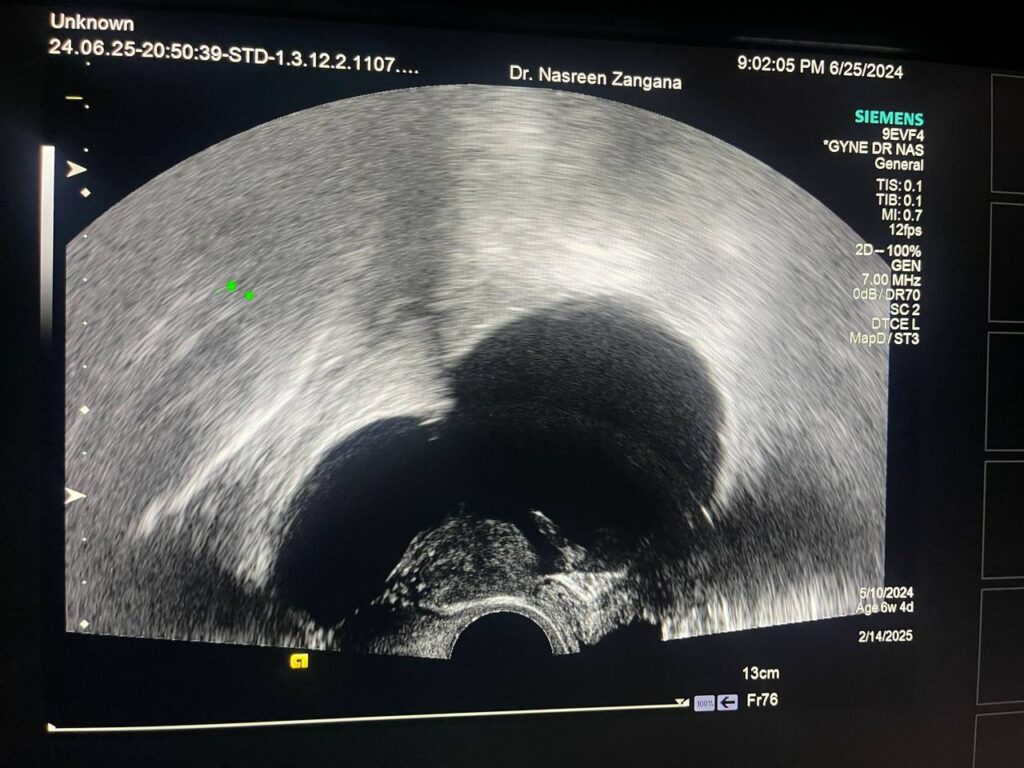

Left adnexal multilocular (< 10) cystic mass > 119x70mm, no extension to surrounding tissue, no ascites, no lymph node, mostly benign, for further study, low grade tumor cannot be excluded